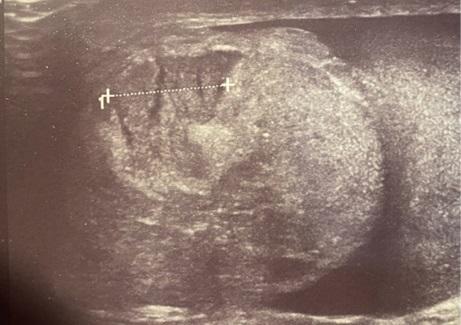

Характерными ультразвуковыми симптомами явились (см. рис. 1):

- гематома позади яичка при сохранении/нарушении целостности его белочной оболочки;

- неоднородность структуры придатка при малом сроке травмы, исключающем развитие посттравматического эпидидимита;

- явное нарушение контура придатка.

Рис. 1. А. Неоднородность структуры придатка с участками «выпадения» кровотока в нём на фоне сохранённого тестикулярного кровотока

Рис. 1. Б. Придаток в поперечном срезе — отёчен, неоднородной структуры